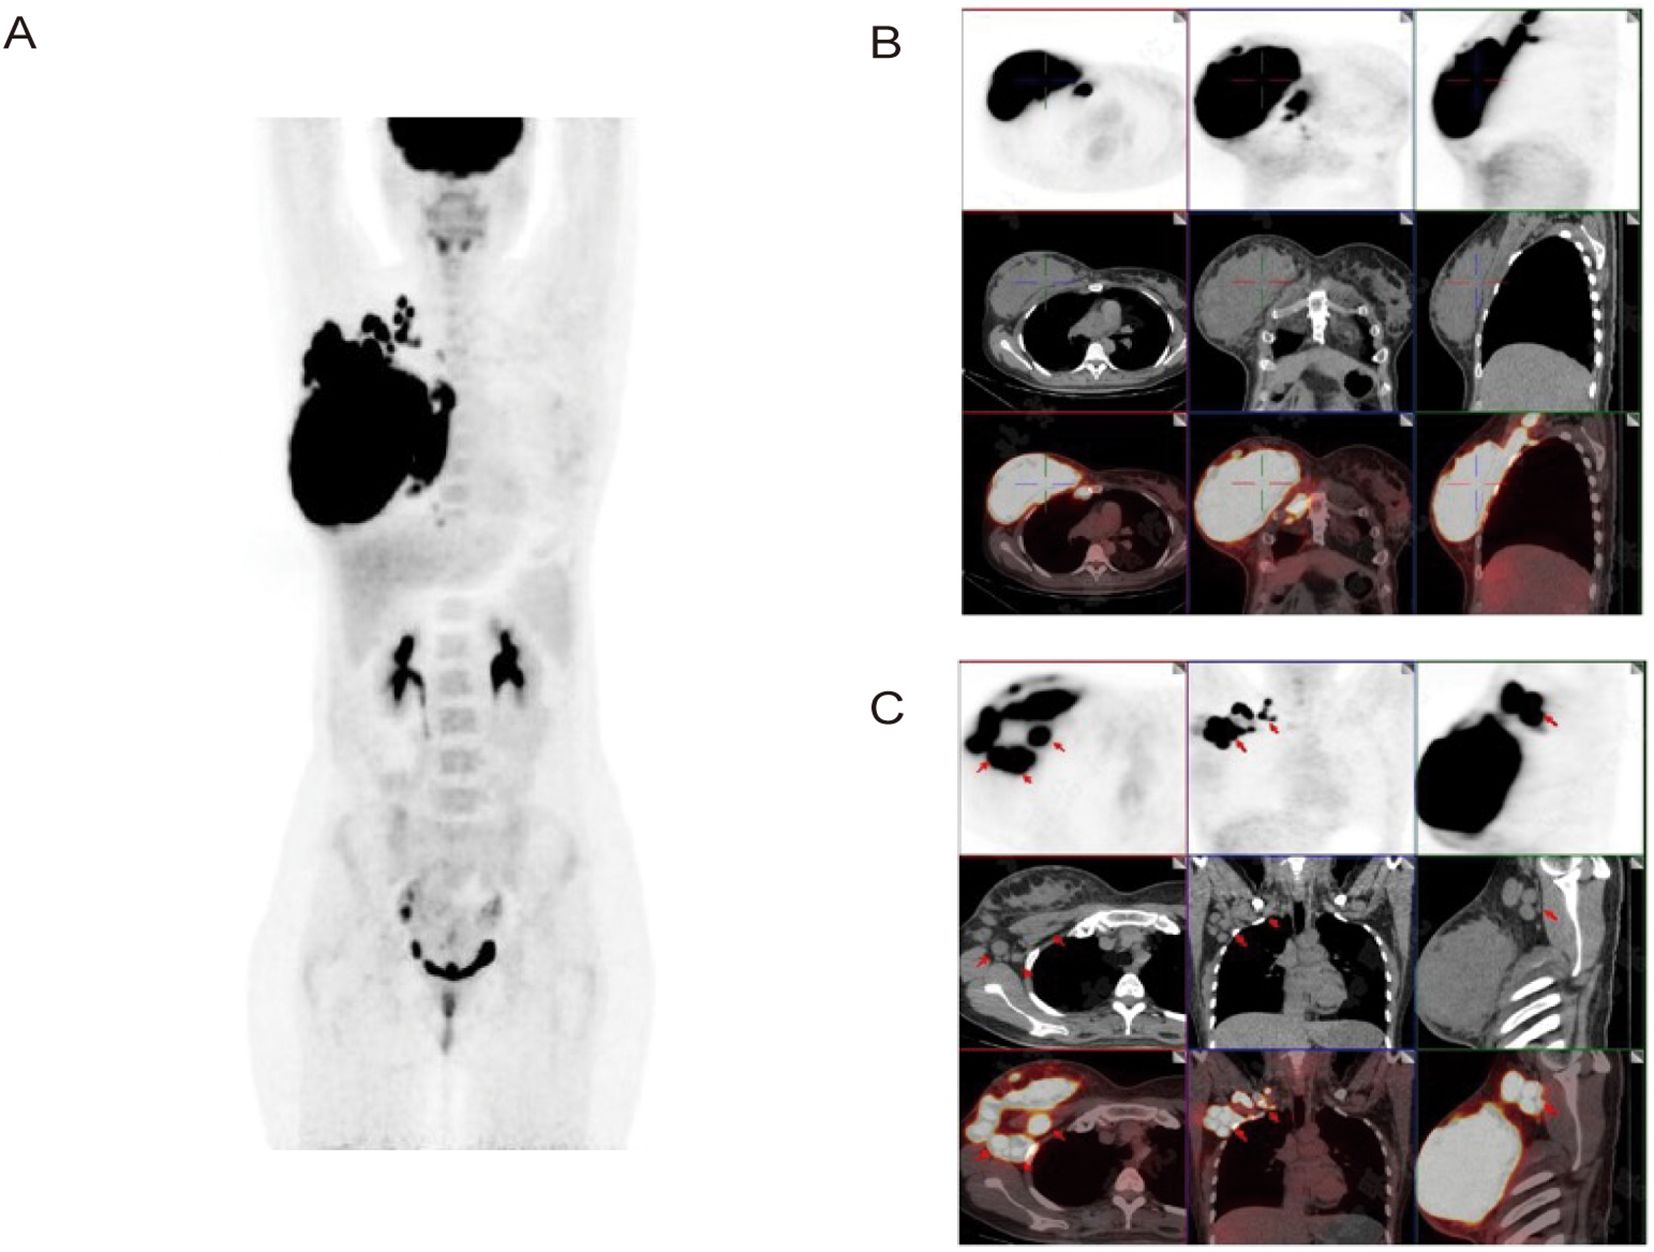

To further clarify the diagnosis and determine the stage of the disease, the clinician ordered additional examinations. Bone marrow biopsy specimen revealed no tumor cell infiltration, and a brain MRI scan did not reveal additional sites of disease, indicating no evidence of hematological and CNS involvement. PET/CT scan was also performed, providing a comprehensive evaluation of metabolic activity in the suspected areas. The scan revealed hypermetabolism of a large right breast mass (standardized uptake value (SUV 40.7)), and multiple enlarged lymph nodes in the right supraclavicular fossa, posterior sternum, right internal milk lymph chain, right thoracic space and right axilla, without evidence of distant adenopathy or secondary lesions (Figure 3). Therefore, the diagnosis of primary DLBCL of the breast was confirmed. Based on these imaging and clinical findings, the patient was staged as IIE according to the Ann Arbor staging, with an International Prognostic Index (IPI) score of one and a Central Nervous System International Prognostic Index (CNS-IPI) score of two.

Figure 3. Axial and coronal reconstructions of PET scan (18F-FDG). (A, B) Demonstrate hypermetabolism of a large right breast mass (SUV 40.7) without evidence of distant adenopathy or secondary lesions. (C) Shows multiple enlarged lymph nodes in the right thoracic space and right axilla.

The patient received three cycles of the Pola-R-CHP regimen (rituximab 600 mg intravenously [IV] on day 0, polatuzumab vedotin 120 mg IV on day 1, cyclophosphamide 1.3 g IV on day 1, doxorubicin 120 mg IV on day 1, and prednisone 100 mg orally [PO] on days 1–5) administered every 21 days, followed by one cycle of the R-MTX regimen (rituximab 600 mg IV and methotrexate 6.3 g continuous intravenous infusion [CIV] over 4 hours). After the 4 cycles of treatment, a repeat PET/CT was performed to assess treatment response, and a complete response (CR) was confirmed. The hypermetabolic foci in the original right breast, right cervical lymph nodes, and right thoracic lymph nodes have all shown a significant decrease in tracer uptake (Deauville score = 2) and there were no new lesions of increased metabolism. The patient demonstrated good compliance. No obvious adverse effects occurred during the treatment period. The patient was satisfied with the correct diagnosis and treatment and was optimistic about the prognosis. Considering the good effect of the treatment plan and economic reasons, the patient has been transferred to a local hospital for further treatment. Timeline of the patient’s diagnosis and treatment was shown in Figure 4.